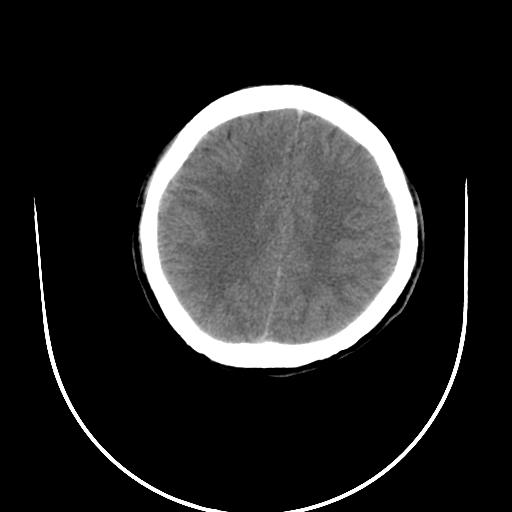

标题: CT10010:女/24岁,癫痫一周,发作时间不固定. [打印本页]

标题: CT10010:女/24岁,癫痫一周,发作时间不固定.

右侧额叶正常吗?

右额叶镰旁饱满.

右侧外侧沟?中央沟?可能有问题,不知以前有没有癫痫过,最好是增强下,排除局部血管畸形等病变

倒数第6幅图中线结构有点偏,而侧脑室额角未见异常,可结合增强扫描。